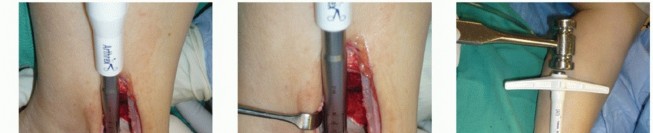

Positioning

The patient is positioned supine (

FIG 3

).

For a lateral OLT, a bolster under the ipsilateral hip typically affords better access to the lateral talar dome. We routinely use a thigh tourniquet.

FIG 3 • Positioning is supine, with easy access to the medial ankle but without too much external rotation, which would make access to the lateral knee cumbersome.